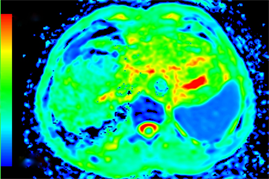

Figure 1. Axial MRI images of HCC patient before TACE treatment. (a) T1-weighted unenhanced image shows a hypointensive lesion in right lobe of liver. (b) Arterial phase contrast-enhanced image shows a heterogeneous enhanceed lesion. (c) ADC map. (d) Dslow map. (e) Dfast map. (f) f map.